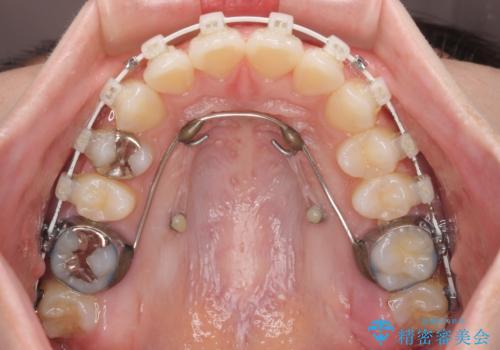

- 上の前歯が下唇に当たる感覚と奥歯の欠損を気にして来院された患者様です。

上顎前歯の突出感は、上顎全体が前方に位置していることが原因であったため、補助装置により上顎全体を後方に移動させることとしました。

後方移動と同時上下歯列をワイヤー装置にて整え、奥歯の欠損部には矯正治療の途中でインプランを埋入していくこととしました。